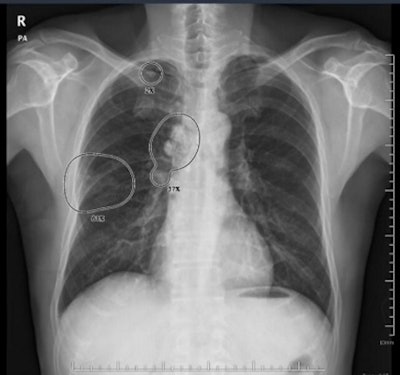

Vuno's AI-powered algorithm Vuno Med-Chest x-ray will be embedded on Samsung's GM85 mobile x-ray system. The software detects and flags suspected chest abnormalities that may be indicators of pulmonary diseases, including tuberculosis and pneumonia.